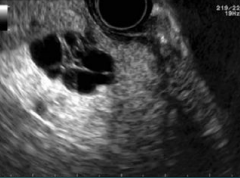

Describe this image

Dx?

An EUS image of a well-defined, hypoechoic cyst with a “central star” and microcysts/septations.

Dx: benign serous cystadenoma